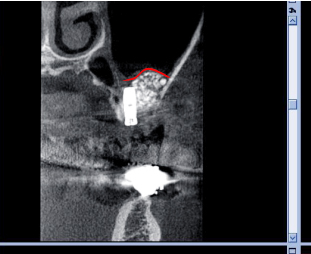

当院で導入した治療後の断面CTです。医科用CTより画像が鮮明なのがお分かりですか。

ポイントは内側の隔壁のところまでサイナスを挙上したところです。これ以上上げると膜を破ってしまいます。

今まで、自分が施術した後のCT画像を見る機会はほとんどありませんでしたが、CT導入で、治療が計画どおりにできていたかチェックと、時間をおいたときにどのようになっているかの再評価ができ、今後の治療方針も大きく変わってくるでしょう。